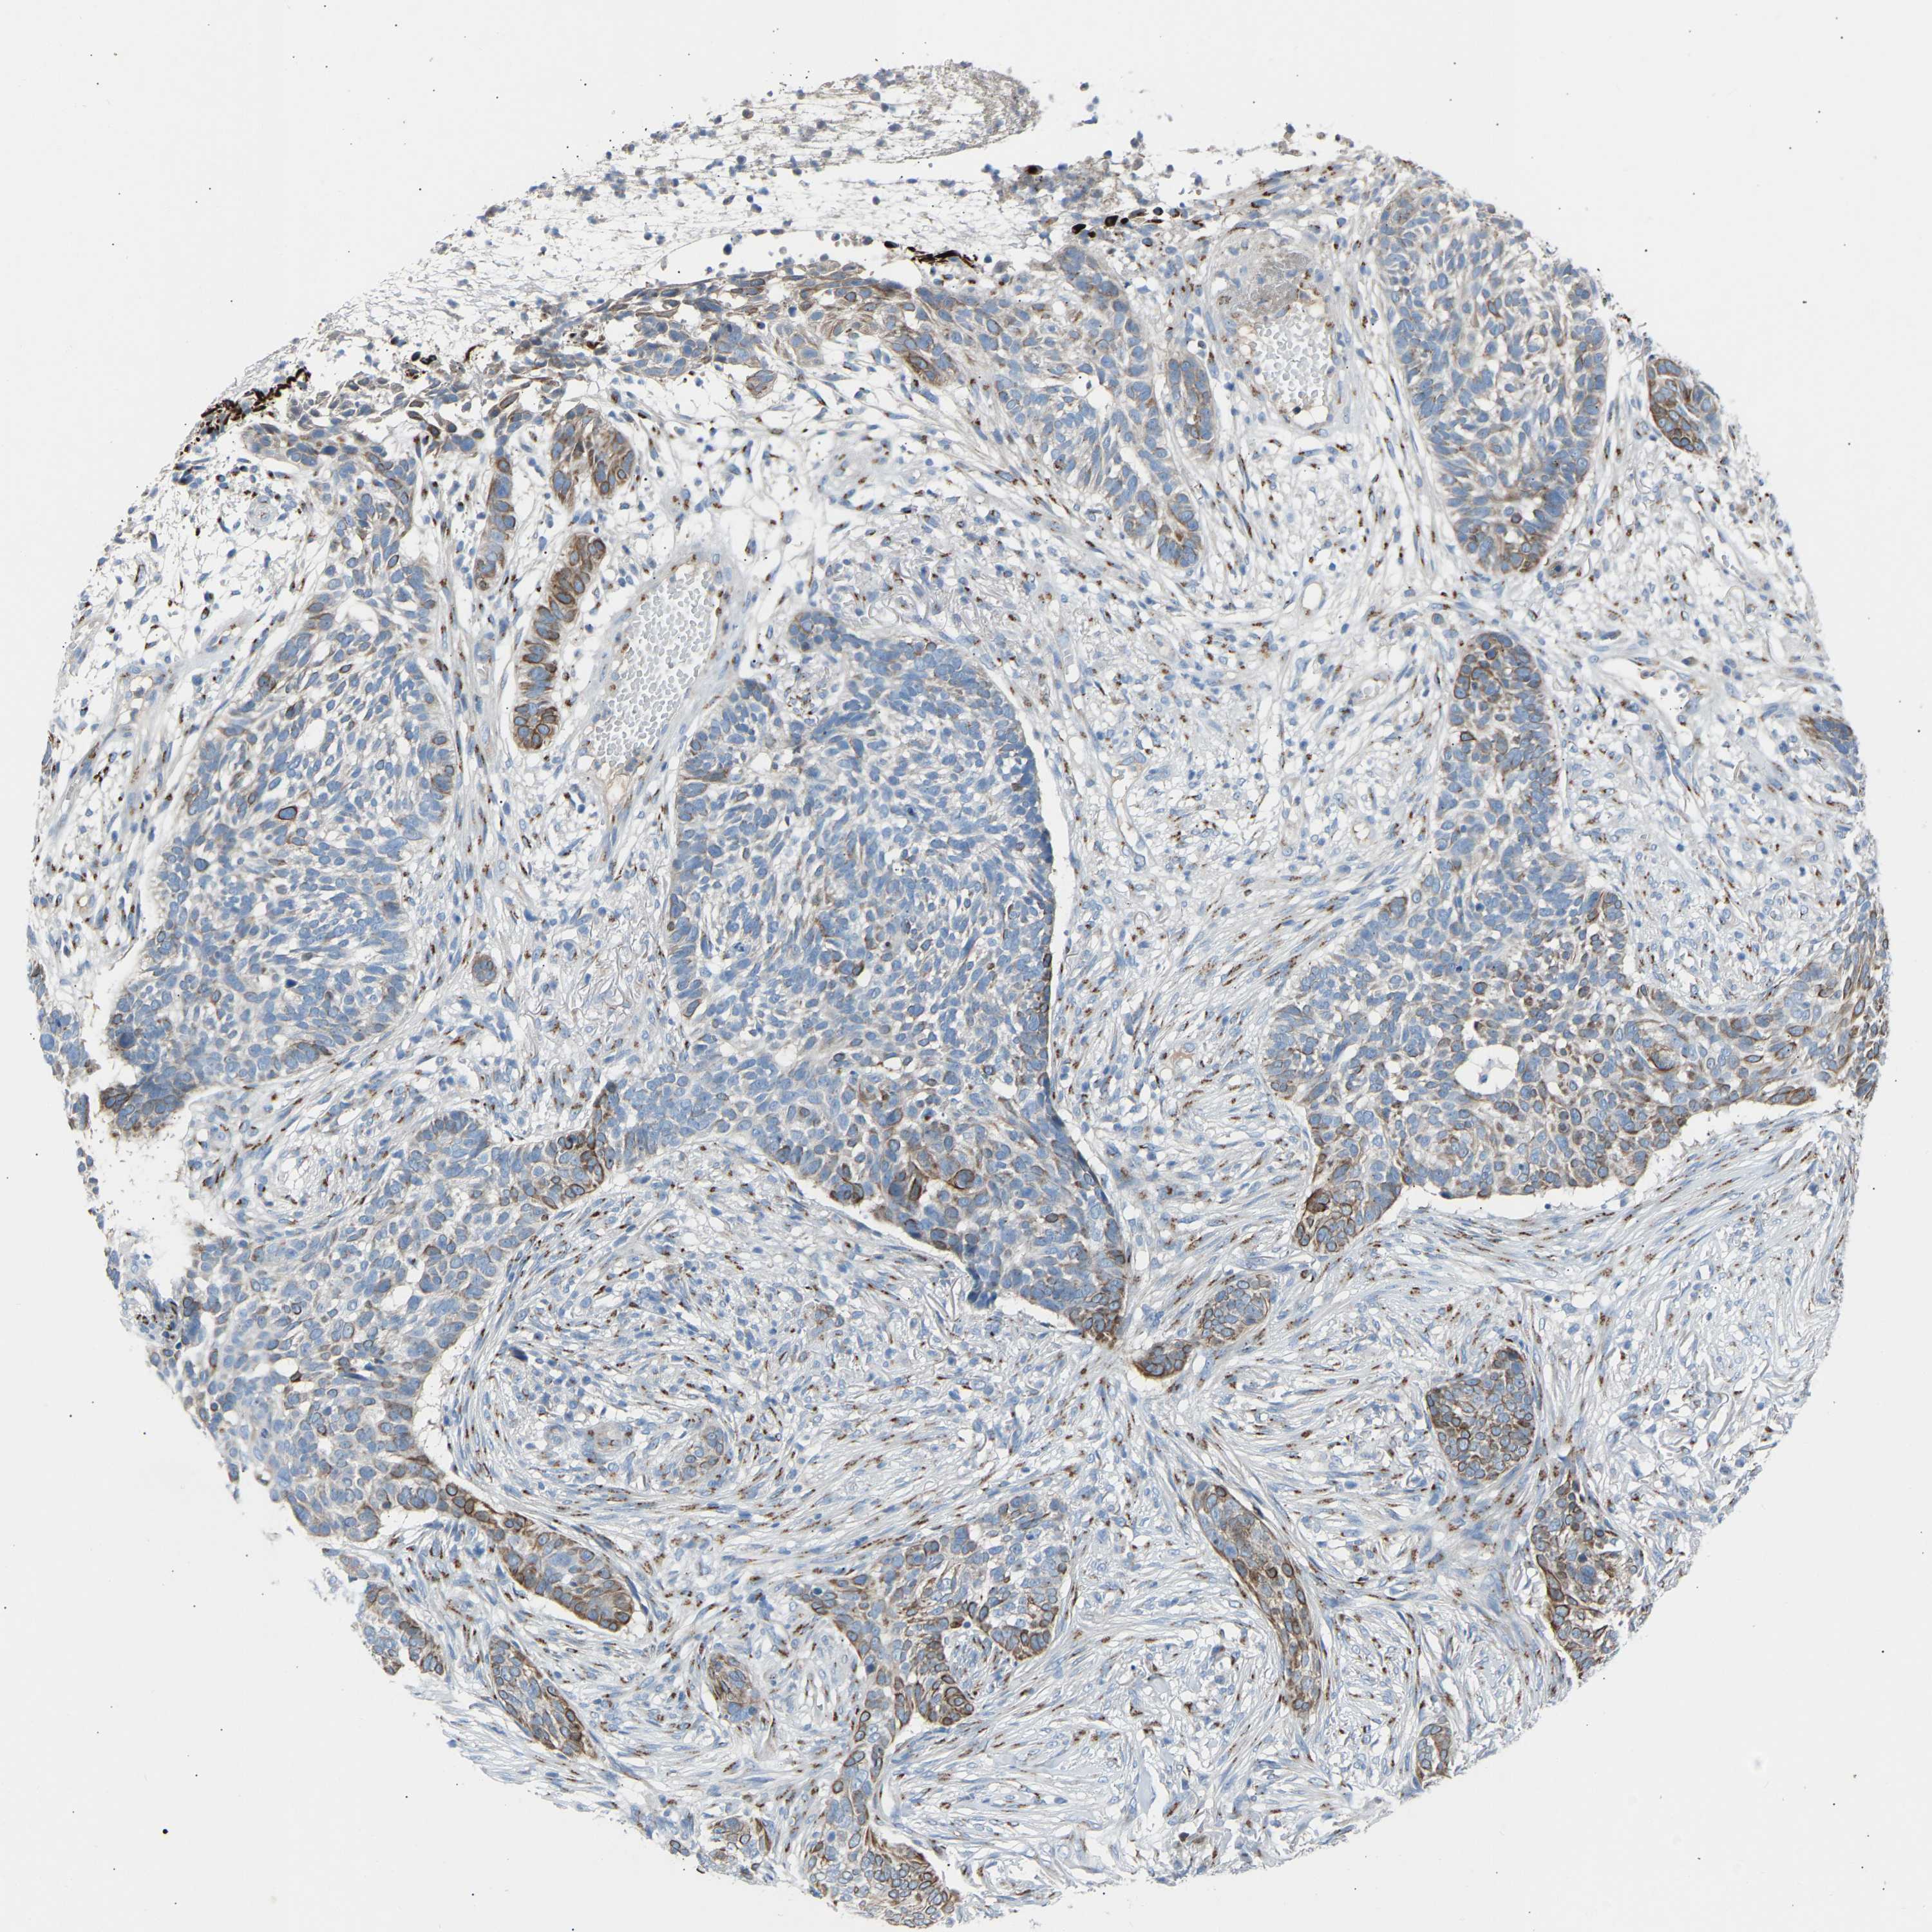

SKIN CANCER - Protein expressioni

A mouse-over function shows sample information and annotation data. Click on an image to view it in a full screen mode. Samples can be filtered based on level of antibody staining by selecting one or several of the following categories: high, medium, low and not detected. The assay and annotation is described here.

Each image is clickable and will lead to virtual microscopy that enables deeper exploration of all samples and also displays staining intensity scores, fraction scores and subcellular localization as well as patient and tissue information for each sample.

Antibody HPA020060

Basal cell carcinoma